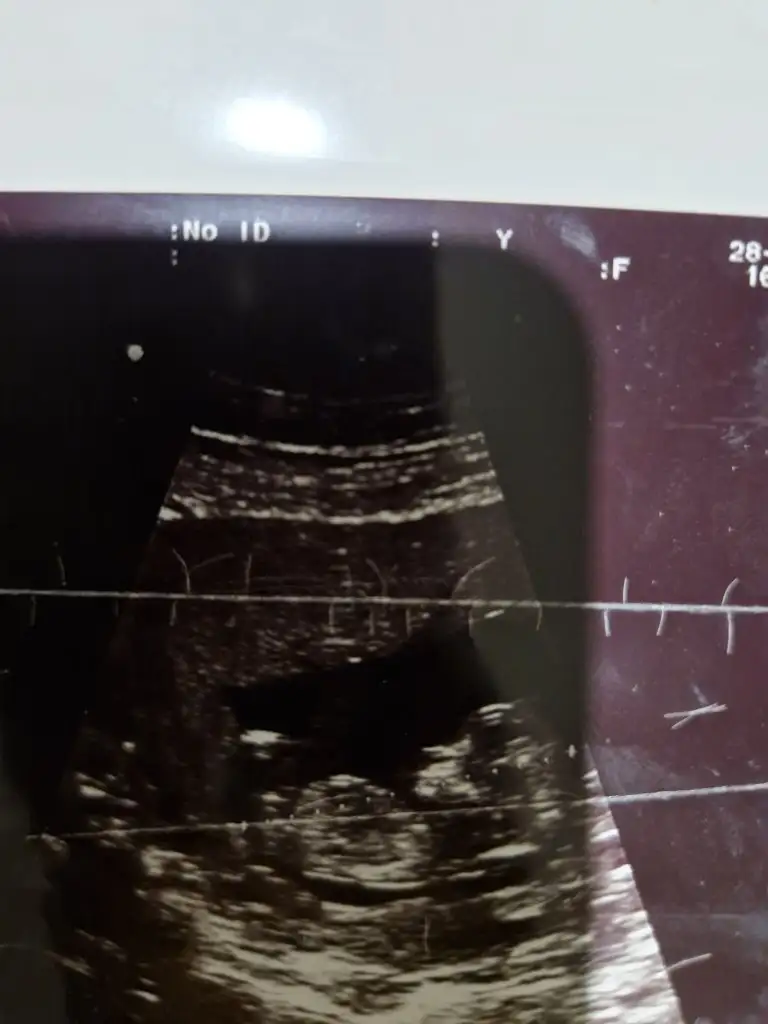

12+1 tahmin yapabilir misjniz

Eklentiler

• IMG_3396.webp

31,6 KB · Görüntüleme: 106